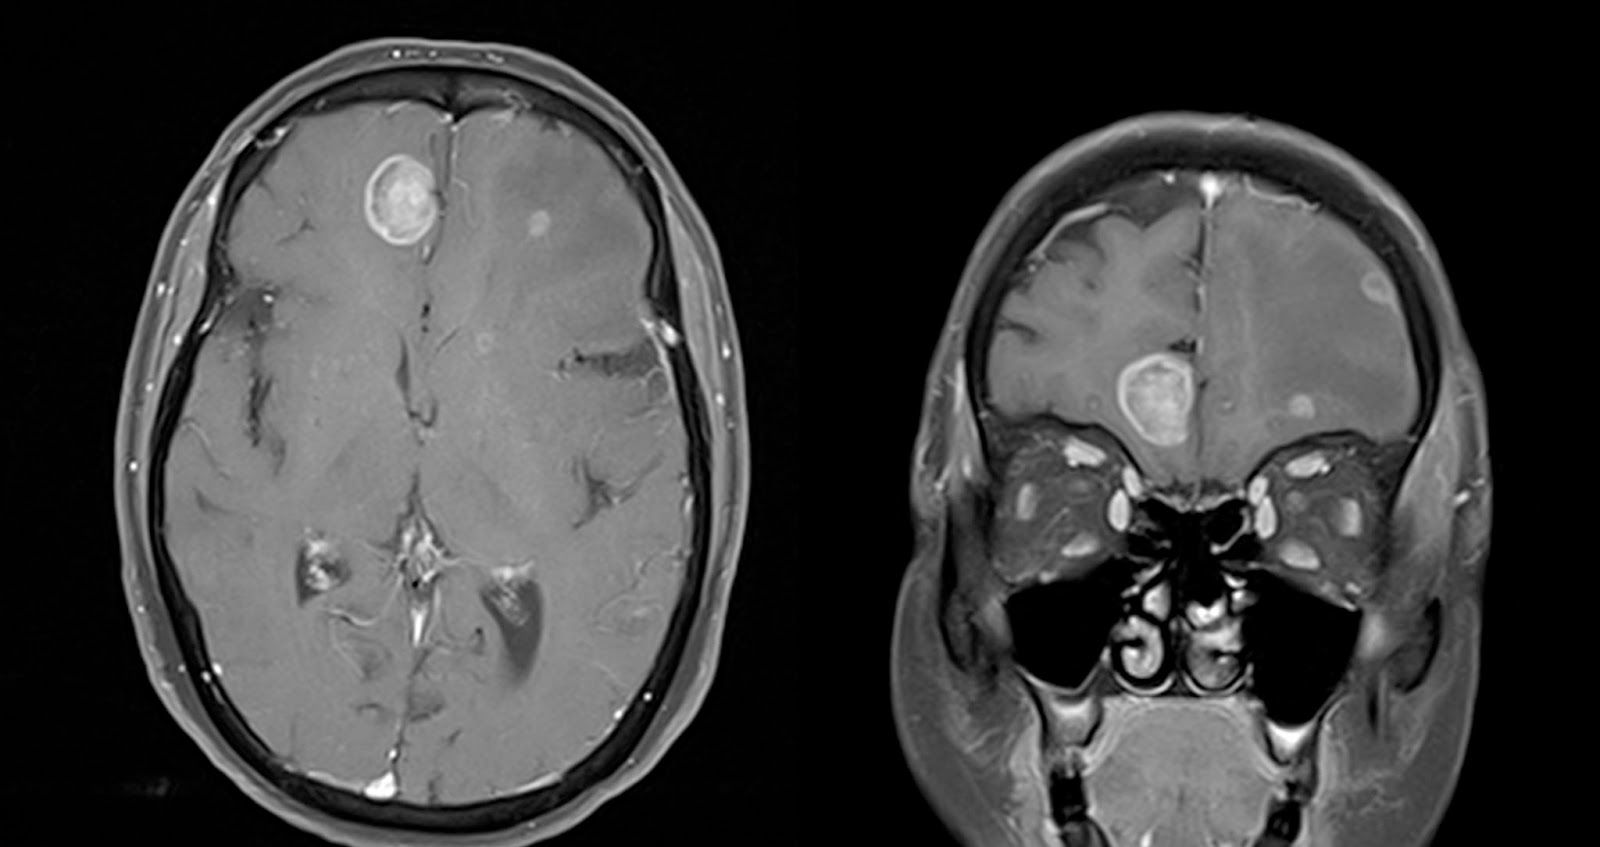

Solitary brain metastasis 14 mm in size identified at the ... 😈

Intracerebral metastases MRI wikidoc 😈